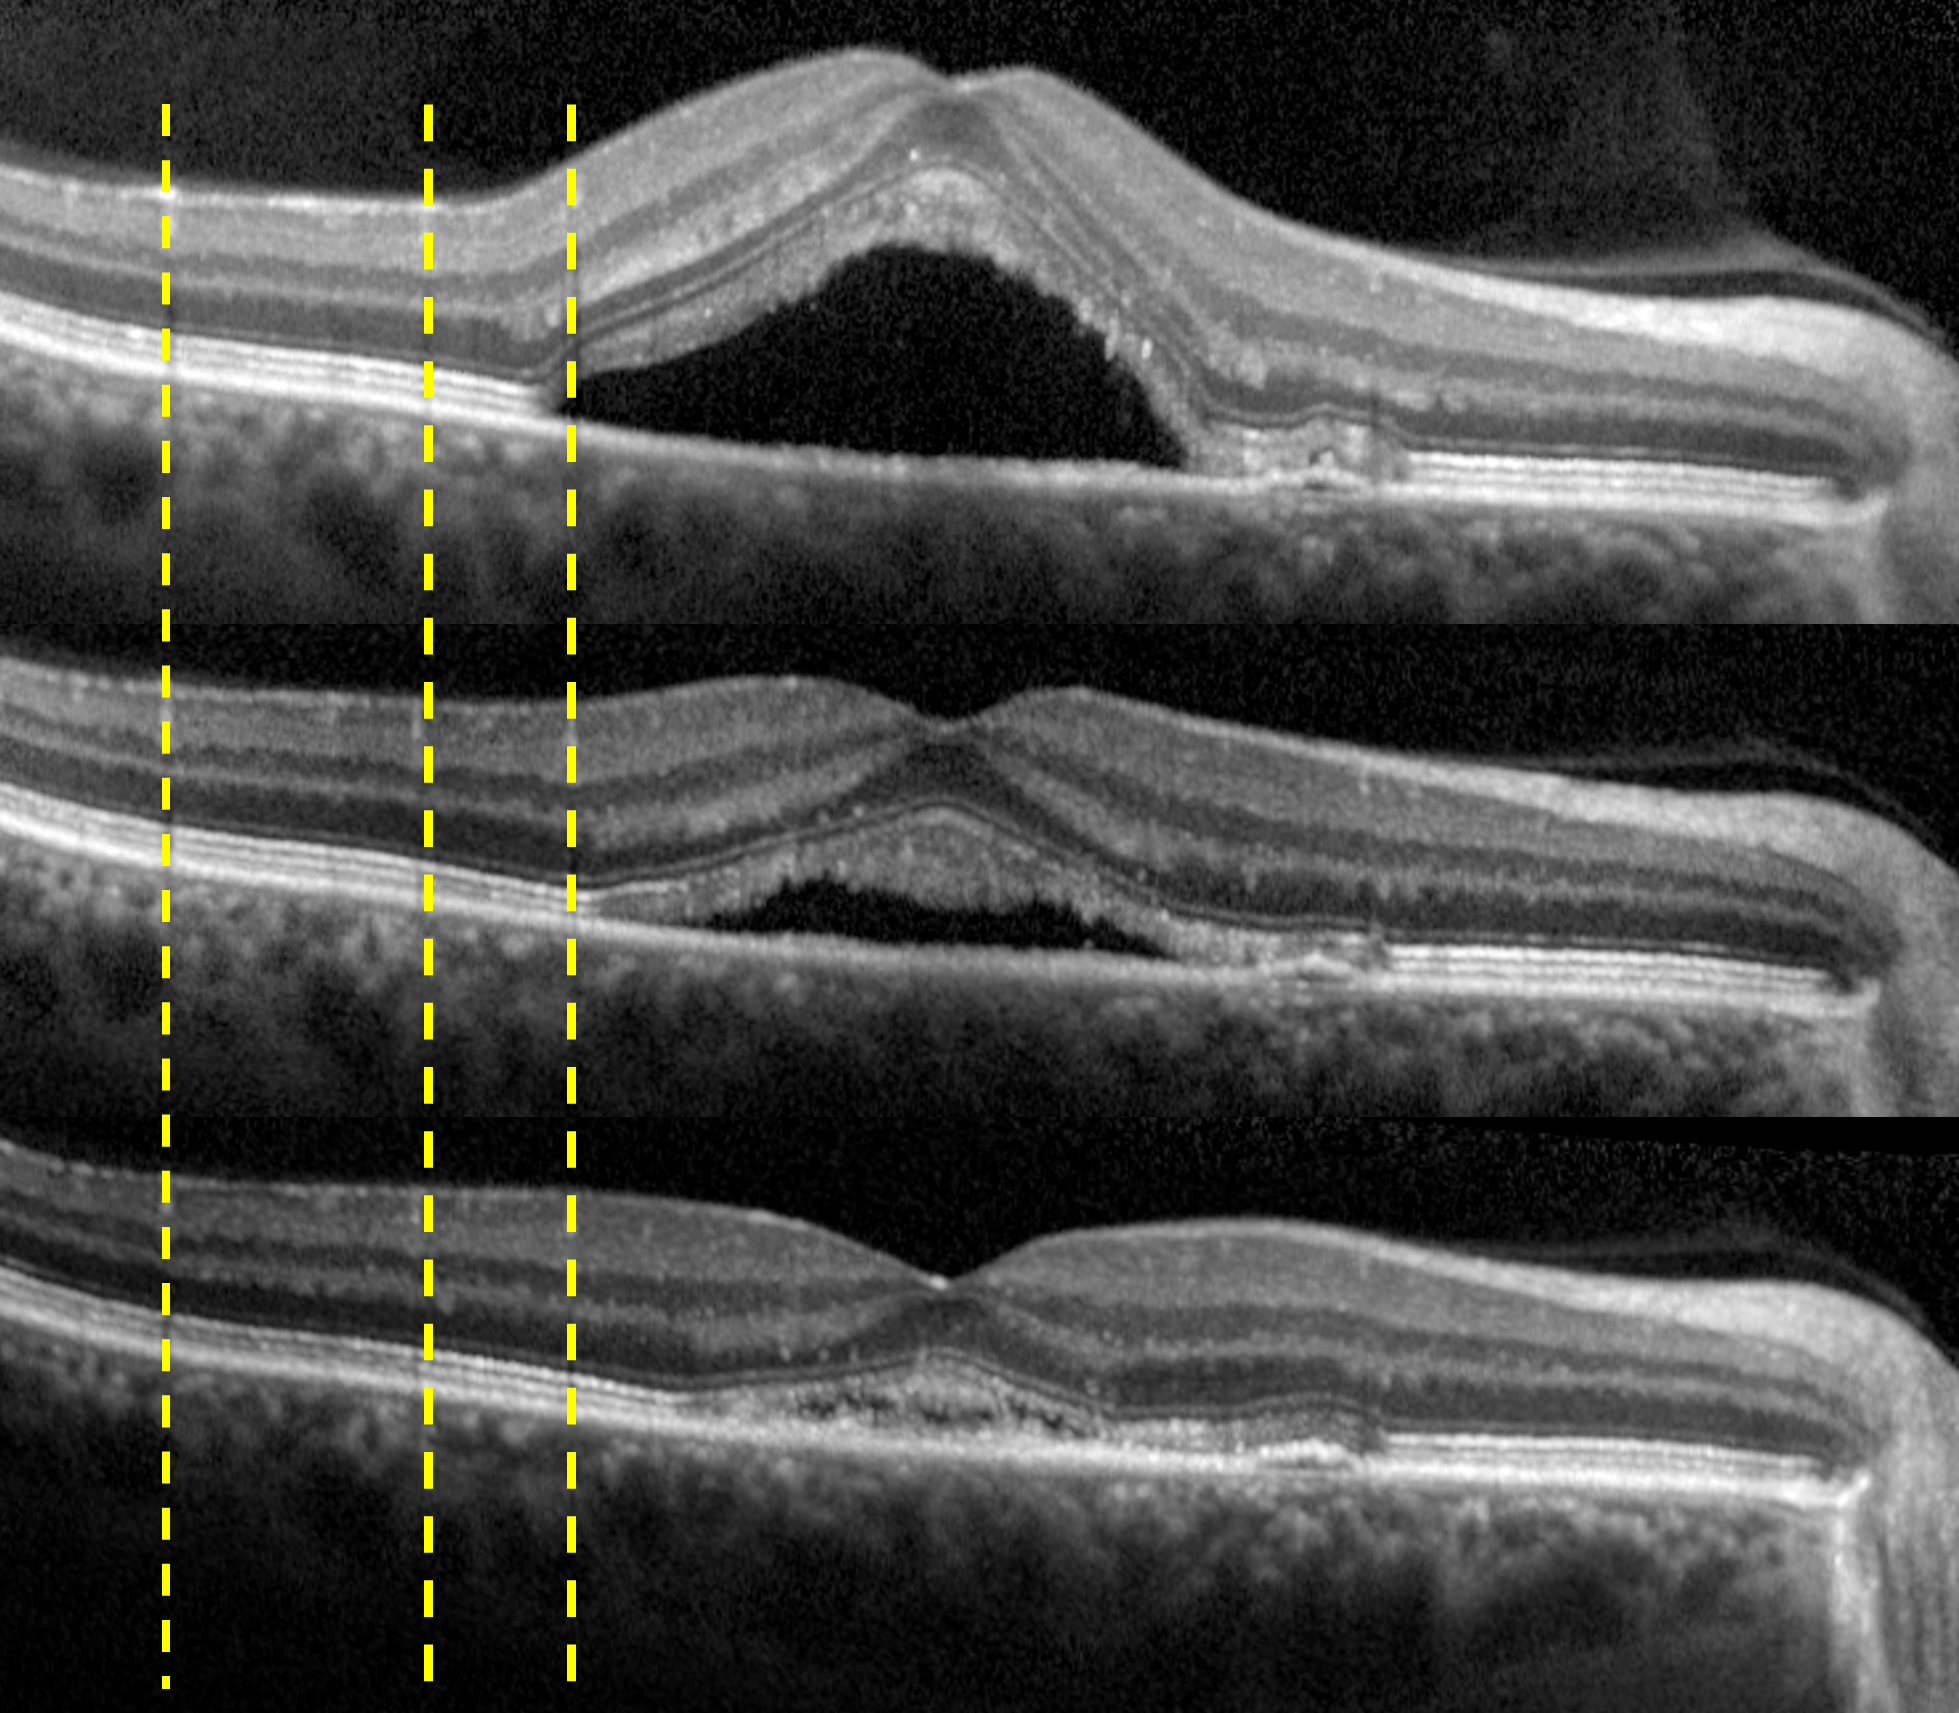

Confocal Scanning Laser Ophthalmoscopy (cSLO)

The SPECTRALIS® confocal scanning laser ophthalmoscope (cSLO) is an innovative technology for imaging the retina. The cSLO provides image detail and clarity not available from fundus photography by combining the selectivity of laser light with the pinpoint resolution of confocal scanning. Often the technology reveals critical diagnostic details not visible with traditional ophthalmoscopy, helping the clinician to document clinical findings. Since cSLO imaging minimizes the effects of light scatter, it can be used effectively even in patients with media opacities or small pupils.